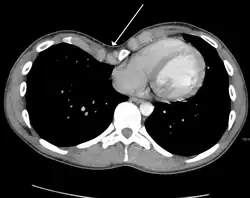

Masses

Axial CT image showing a large left sided mass that appears attached to the pleura.

Masses such as tumors can also cause compression and displacement of mediastinal structures. There are various mediastinal tumors, and they are classified by their location in the chest. Notable examples include germ cell tumors and lymphomas.[12] Teratomas are a class of germ cell tumors that arise in the chest due to failure of germ cell migration during development. They can expand to large sizes and cause hemoptysis and pleural effusion. Radiographic features of teratomas typically include fluid and fat but also muscle, teeth, and bones inside the mass.[13]